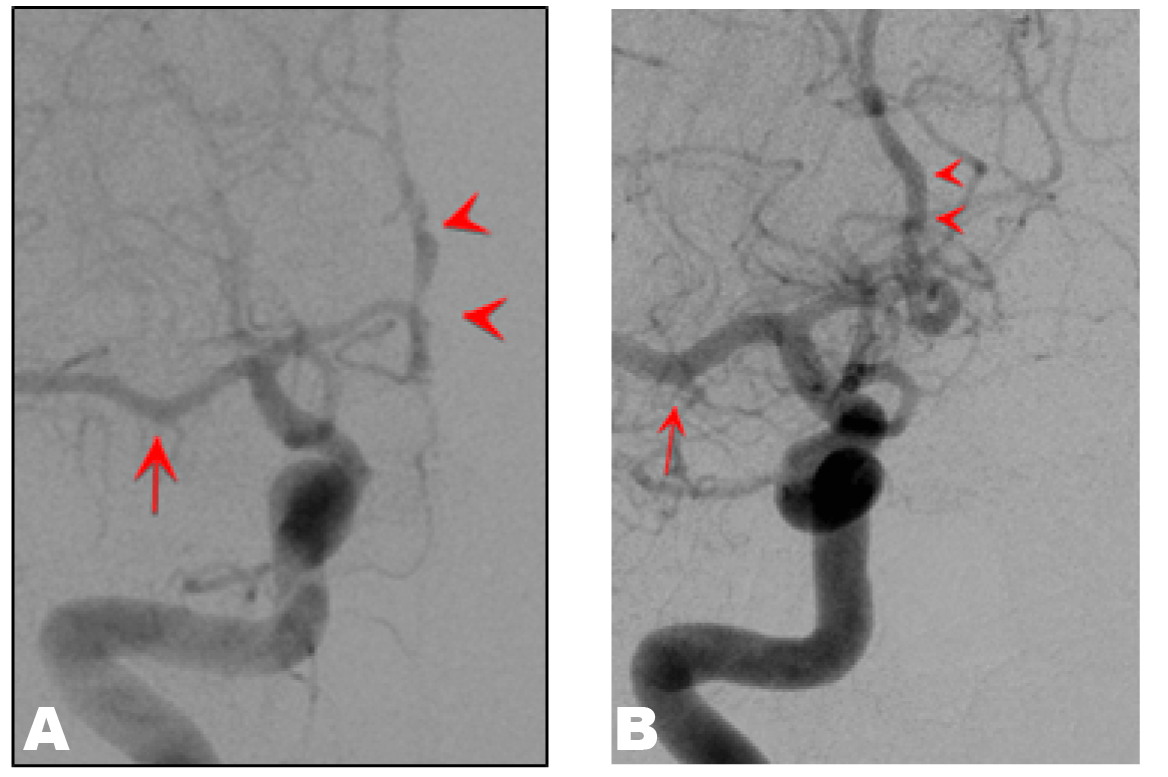

On hospital day 2, TCCFI indicated MCA peak systolic velocities (PSV) of 330 (right side) and 266 (left side) cm/s. (Figure 2) On hospital day 3, nicardipine was discontinued and replaced by oral administration of a calcium blocking agent, which maintained blood pressure at approximately 130/80 mmHg. Headache was also relieved from hospital day 7. TCCFI on hospital day 13 showed that the PSV of both MCAs had improved to approximately 150 cm/s. MRA on hospital day 14 and at 43rd day postpartum revealed progressive improvement of the lesions in the ACAs and MCAs. (Figure 1B-C) On hospital day 17, cerebral angiography showed improvement of segmental changes of the ACA and a larger diameter of the MCA compared to that in previous tests. (Figure 3) MRI scan of head at 43rd day postpartum showed decreased caudate hemorrhage and disappearance of the lesions in the corpus callosum.

Figure 3: Cerebral angiography (A) On hospital day 3, and (B) On hospital day 17. (A): Segmental stenosis and dilatation at the origin of the A2 segment of the anterior cerebral arteries (arrow head). The middle cerebral arteries was constricted, but neither focal stenosis nor dilatation was observed (arrow). (B) Segmental changes of anterior cerebral arteries were improved and the diameter of the middle cerebral arteries was larger than that in the earlier test.